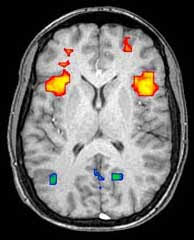

Using electroencephalogram (EEG) scans of various humans' heads, scientists were able to deduce unique patterns in which the brain's neurons fired in response to certain terms. Each word, when flashed for under a second, imbued its own brain-spanning tracks through the users' grey matter, the pathway of which was then recorded and later used for authentication of the specific person.

By focusing solely on the region of the brain that reads and recognizes words, the scientists were able to eliminate any interloping "chatter" going on during the rest of the mind's business-as-usual. This allowed them to zero in on the desired authentication indicators.

| "OK, every time it lights up yellow, let Bill into the nuke lab. If anything else lights up, have him arrested for using meth." (Image courtesy tek-think.com.) |